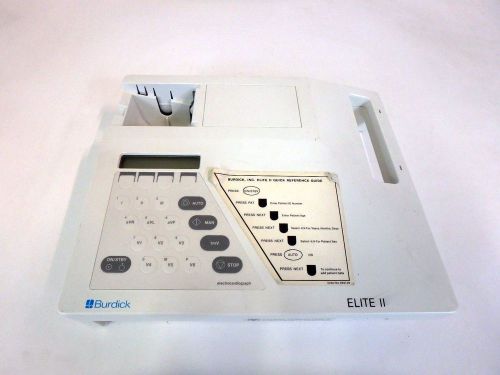

Burdick Elite II EKG ECG Medical Electrocardiograph